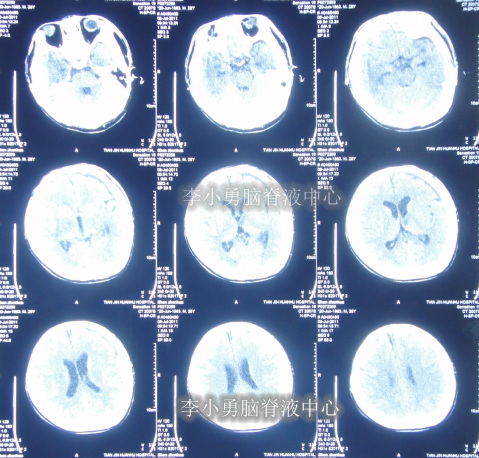

脑室外引流术后5天即2011年6月25日,查头部CT颅内仍有出血(图-4)。

图-4:2011年6月25日头部CT

拔除脑室外引流术后1天即2011年6月29日,头部CT示颅内出血基本消失(图-5),给予腰大池引流术。

图-5:2011年6月29日头部CT